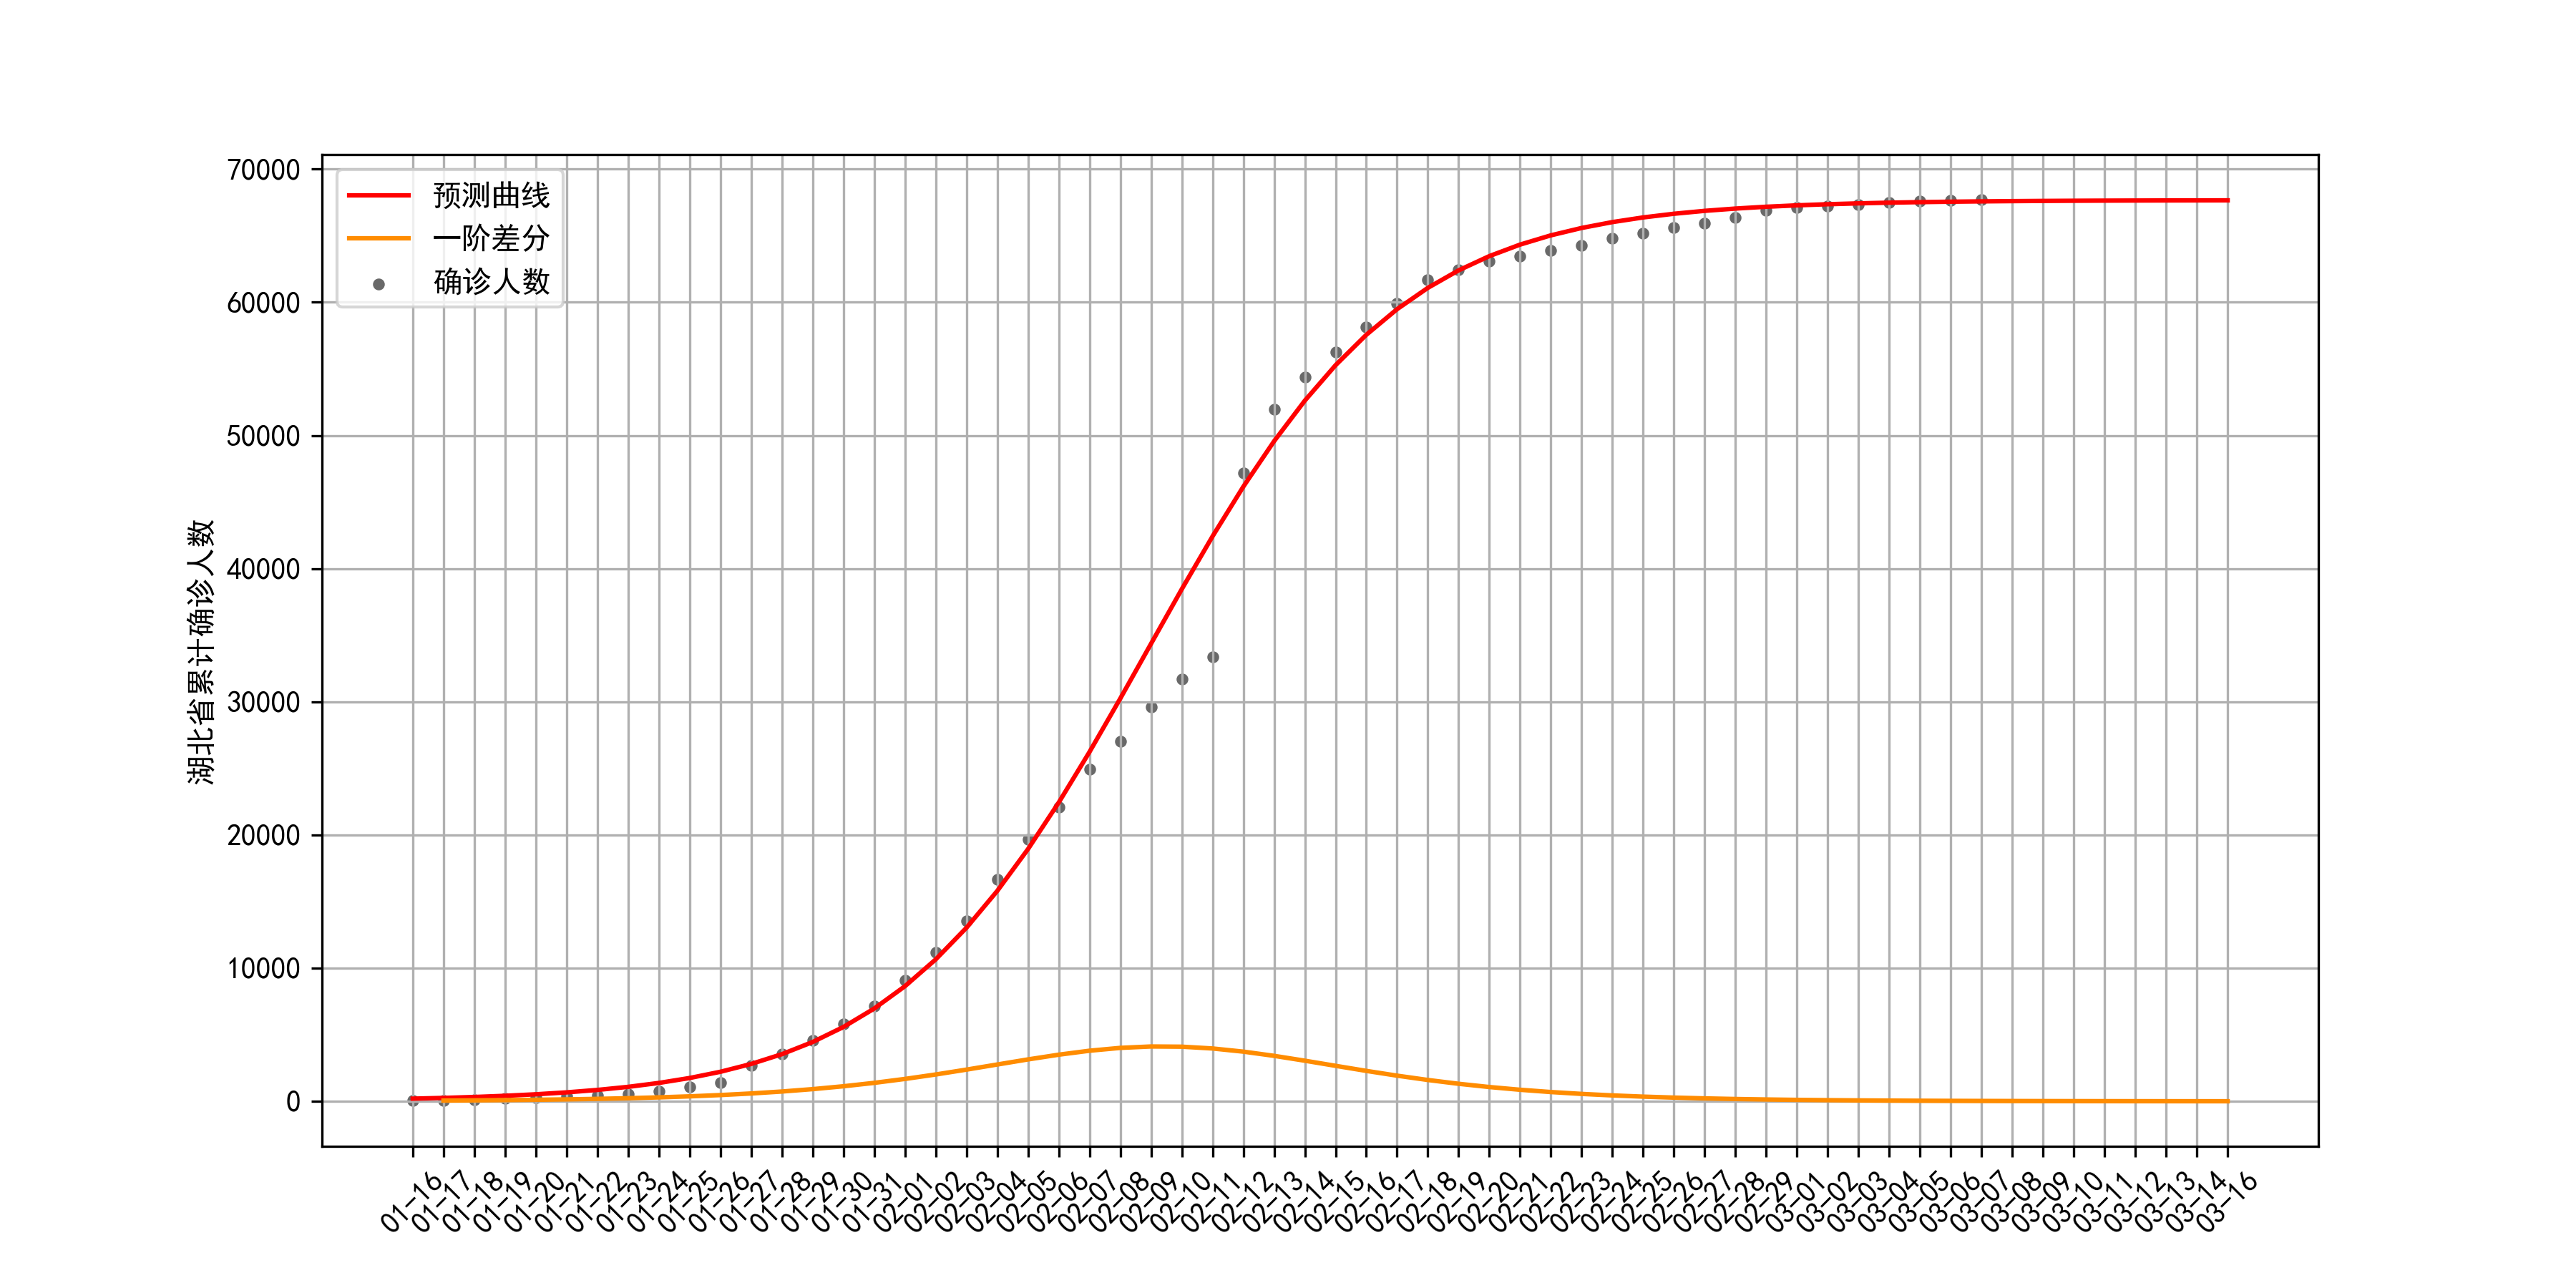

2. 用Logistic模型拟合疫情

考虑到湖北省内与湖北省外存在异质性,下面将用Logistic模型分别对湖北省与湖北省外的累计确诊人数进行拟合。首先需要获取累计确诊人数,数据来源为WindQuant提供的Wind数据接口,更多数据下载方法见获取COVID-19疫情历史数据的n种方法。

然后使用Scipy.optimezi库的curve_fit函数对Logistic曲线进行非线性最小二乘拟合。待定参数包括

2.1 湖北省

湖北省疫情拟合结果:最大容量

r为0.24。疫情的拐点发生在2月8日前后,这也是疫情增长最快一段时期,在这段时间内,由于疫情的快速增长和医疗资源的相对匮乏,官方公布的确诊人数失真严重。从拟合结果来看,当前疫情已经到达尾声。